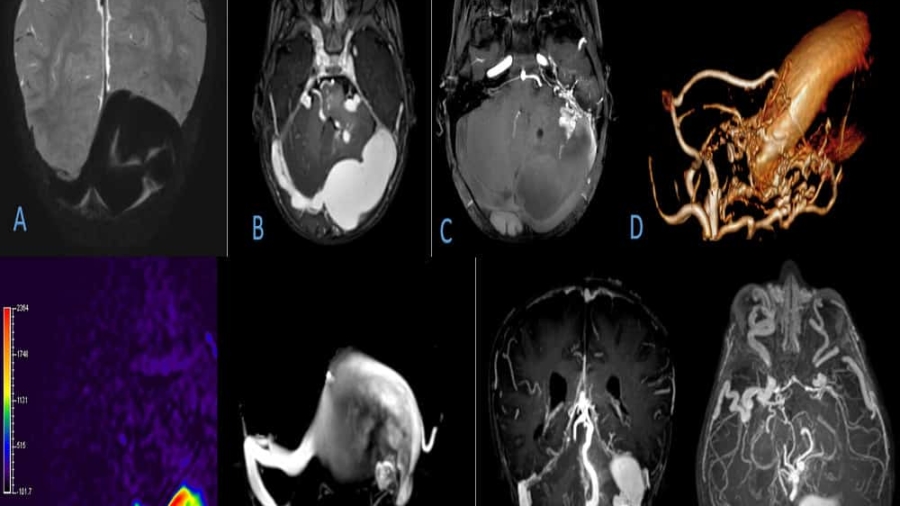

11 year old female child presented with history of right sided hearing loss, vertigo and imbalance since 6 months, right facial numbness, facial asymmetry and difficulty swallowing since 3 months, headache and vomiting since 1 month duration.